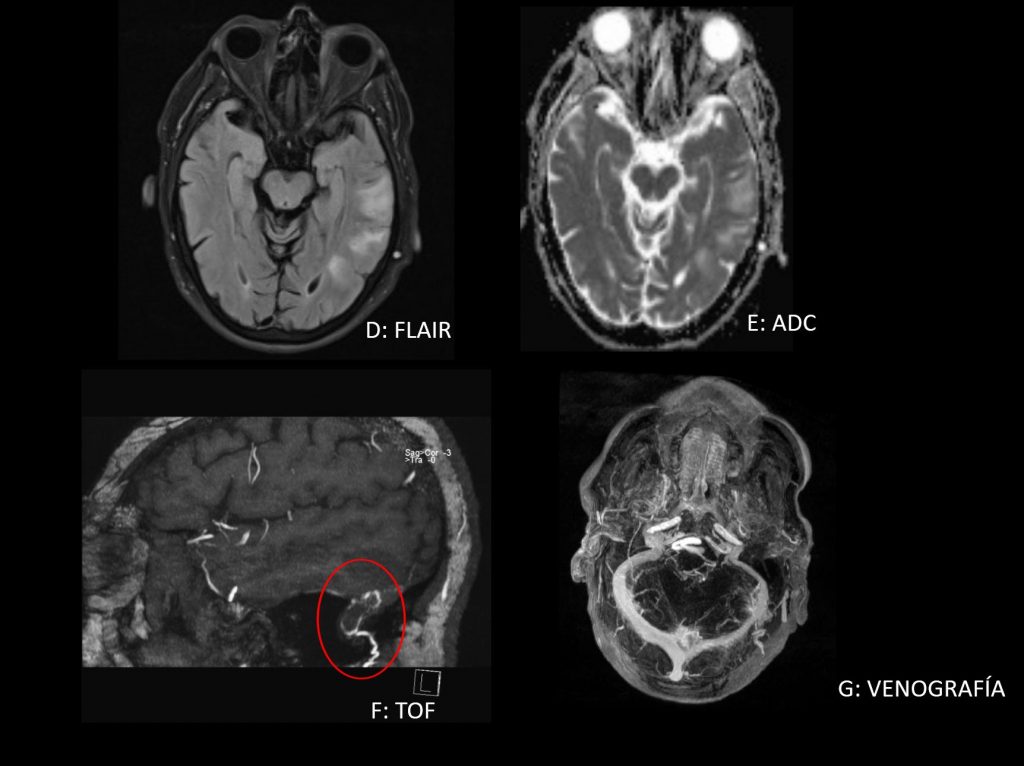

RM cerebral: Hiperseñal en FLAIR (D) con difusión facilitada (E) compatible con edema vasogénico. Hiperseñal en TOF rodeando a la pared del seno sigmoide a partir de una rama occipital hipertrófica de la ACE (F). Los senos venosos están permeables (G).

Debemos sospechar FAV en estudios de TC o RM: – Estructuras vasculares prominentes SIN nidus. – Aumento de volumen en perfusión. – Edema con microhemorragia en T2*. – Hiperseñal venosa en TOF. – Relleno venoso precoz en estudios dinámicos.